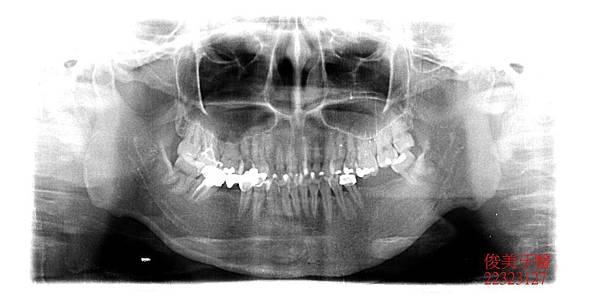

患者年約30歲,女性,於門診時表示,又蛀牙了,經醫師檢查後發現,患者因為缺牙及齒列不整

齊導致牙弓變形、咬合不佳,很多牙縫超會塞東西,且後牙未修復導致前牙牙齒有咬裂的現象,

因此建議患者考慮全口重建,將口內所有的問題分析給患者瞭解,再進行療程。

蛀牙過多,且深。牙弓形狀已非標準形態。

下顎狀況 。